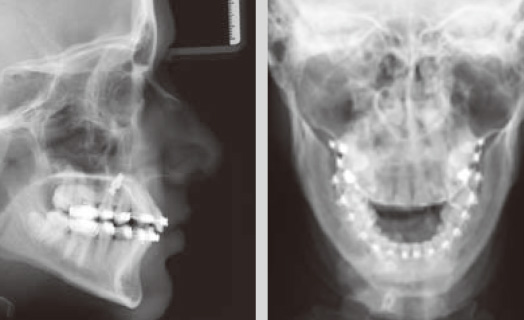

CTレントゲン、セファロレントゲンは最先端のデジタルレントゲンオーソフォスXG。

歯の根が生えているのは、アゴの骨のなか。どうしても診断にはレントゲン撮影が欠かせません。当院で採用している最新式の歯科用CTレントゲン装置は、医科用の一般的な頭部CTに比べ、約1/30の放射線量による撮影が可能で、目には見えない体への負担を軽減します。